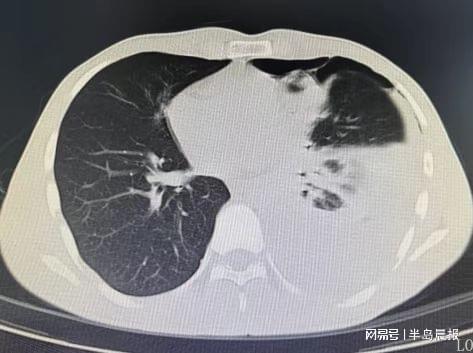

胸部CT检查结果让所有人警惕:小张左侧胸腔积聚大量浑浊积液,几乎占胸腔近三分之一,已压迫肺部引发气胸,不符合普通肺炎的影像学特征。当天,他就被收治入院。